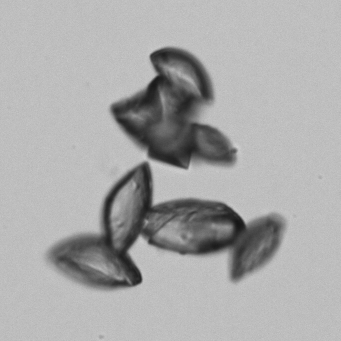

Uric acid - Irregular

Uric acid crystals occur with increased uric acid excretion or in acidic urine (pH < 5.8). Uric acid is a waste product of purine metabolism; purines are chemical compounds such as adenine and guanine (DNA components), caffeine and xanthine, and are mainly found in meat (products). The crystals can take various forms: usually diamond- or diamond-shaped plates, hexagonal plates, cylindrical structures (barrels), elongated prisms, star-shaped, spherical, needle-shaped or dumbbell-shaped crystals. They are usually yellowish to brown in color and show strong, polychromatic birefringence. They may precipitate when the urine has been kept cold prior to analysis.

The yellow discoloration of the crystals in this preparation is caused by fixation with glutaraldehyde.